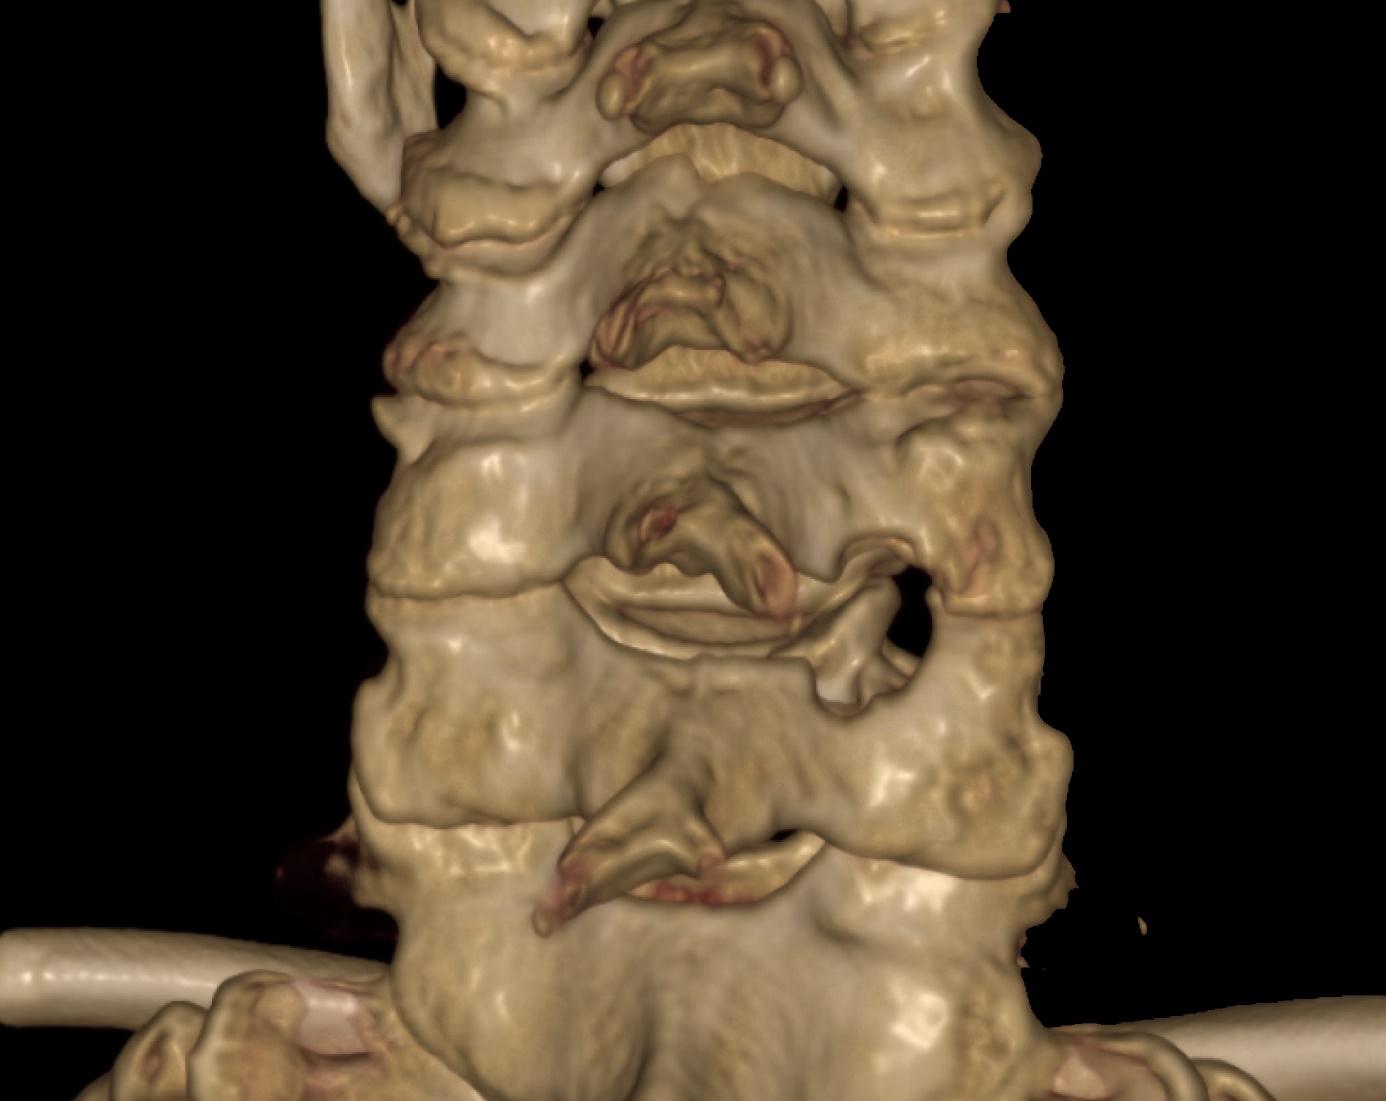

För 15 år sedan gjordes nästan hälften av alla totala höftproteser med lateralt snitt. Därefter har bakre snitt vunnit mark och numera utförs ungefär 65% med bakre och 34% med lateralt snitt. Huvudskillnaden mellan lateralt och bakre snitt är att tillgång till höftleden görs genom att den främre delen av höftens abduktormuskler (gluteus medius och minimus) på det första, och de korta utåtrotatorerna på det senare, frigörs (Fig 1 och 2).

Figur 1: Vid lateralt snitt frigörs den främre delen av gluteus medius senan tillsammans med den främre delen av vastus lateralis fäste från trochanter major för att komma åt höftleden. Främre kapsel kan frigöras eller tas bort helt. De frigjorda senorna sys sedan tillbaka till trochanter när protesen är insatt.

Proximalt

Figur 2: Vid bakre snitt frigörs utåtrotatorerna från trochanter major för att komma åt höftleden. Bakre kapsel frigörs men besparas och sys tillbaka till trochanter tillsammans med utåtrotatorerna när protesen är insatt.

dock visat att den risken har successivt minskat och ligger numera på samma nivå som risken efter lateralt snitt. Modernare implantat och vetskapen att bakre snitt är mindre förlåtande än lateralt kan ha bidragit till att bakre snitt har blivit säkrare. Betydligt färre studier har försökt studera hälta med hjälp av gånganalys och patientenkäter. Några har visat en större risk för hälta efter lateralt snitt, men andra har inte kunnat påvisa någon skillnad mellan snitten. Man får dock komma ihåg att studier om hälta är betydligt mindre (ofta < 100 patienter) än registerstudier och har därför en lägre förmåga att hitta generaliserbara skillnader. En intressant studie, som undersökte hur enskilda höftmuskler blir påverkade av ärrbildning och fettomvandling efter höftledsplastik, visade att abduktormuskulatur, som är väsentlig för en normal gång, blir betydligt mer påverkad efter lateralt snitt än vad utåtrotatorer blir efter bakre snitt.